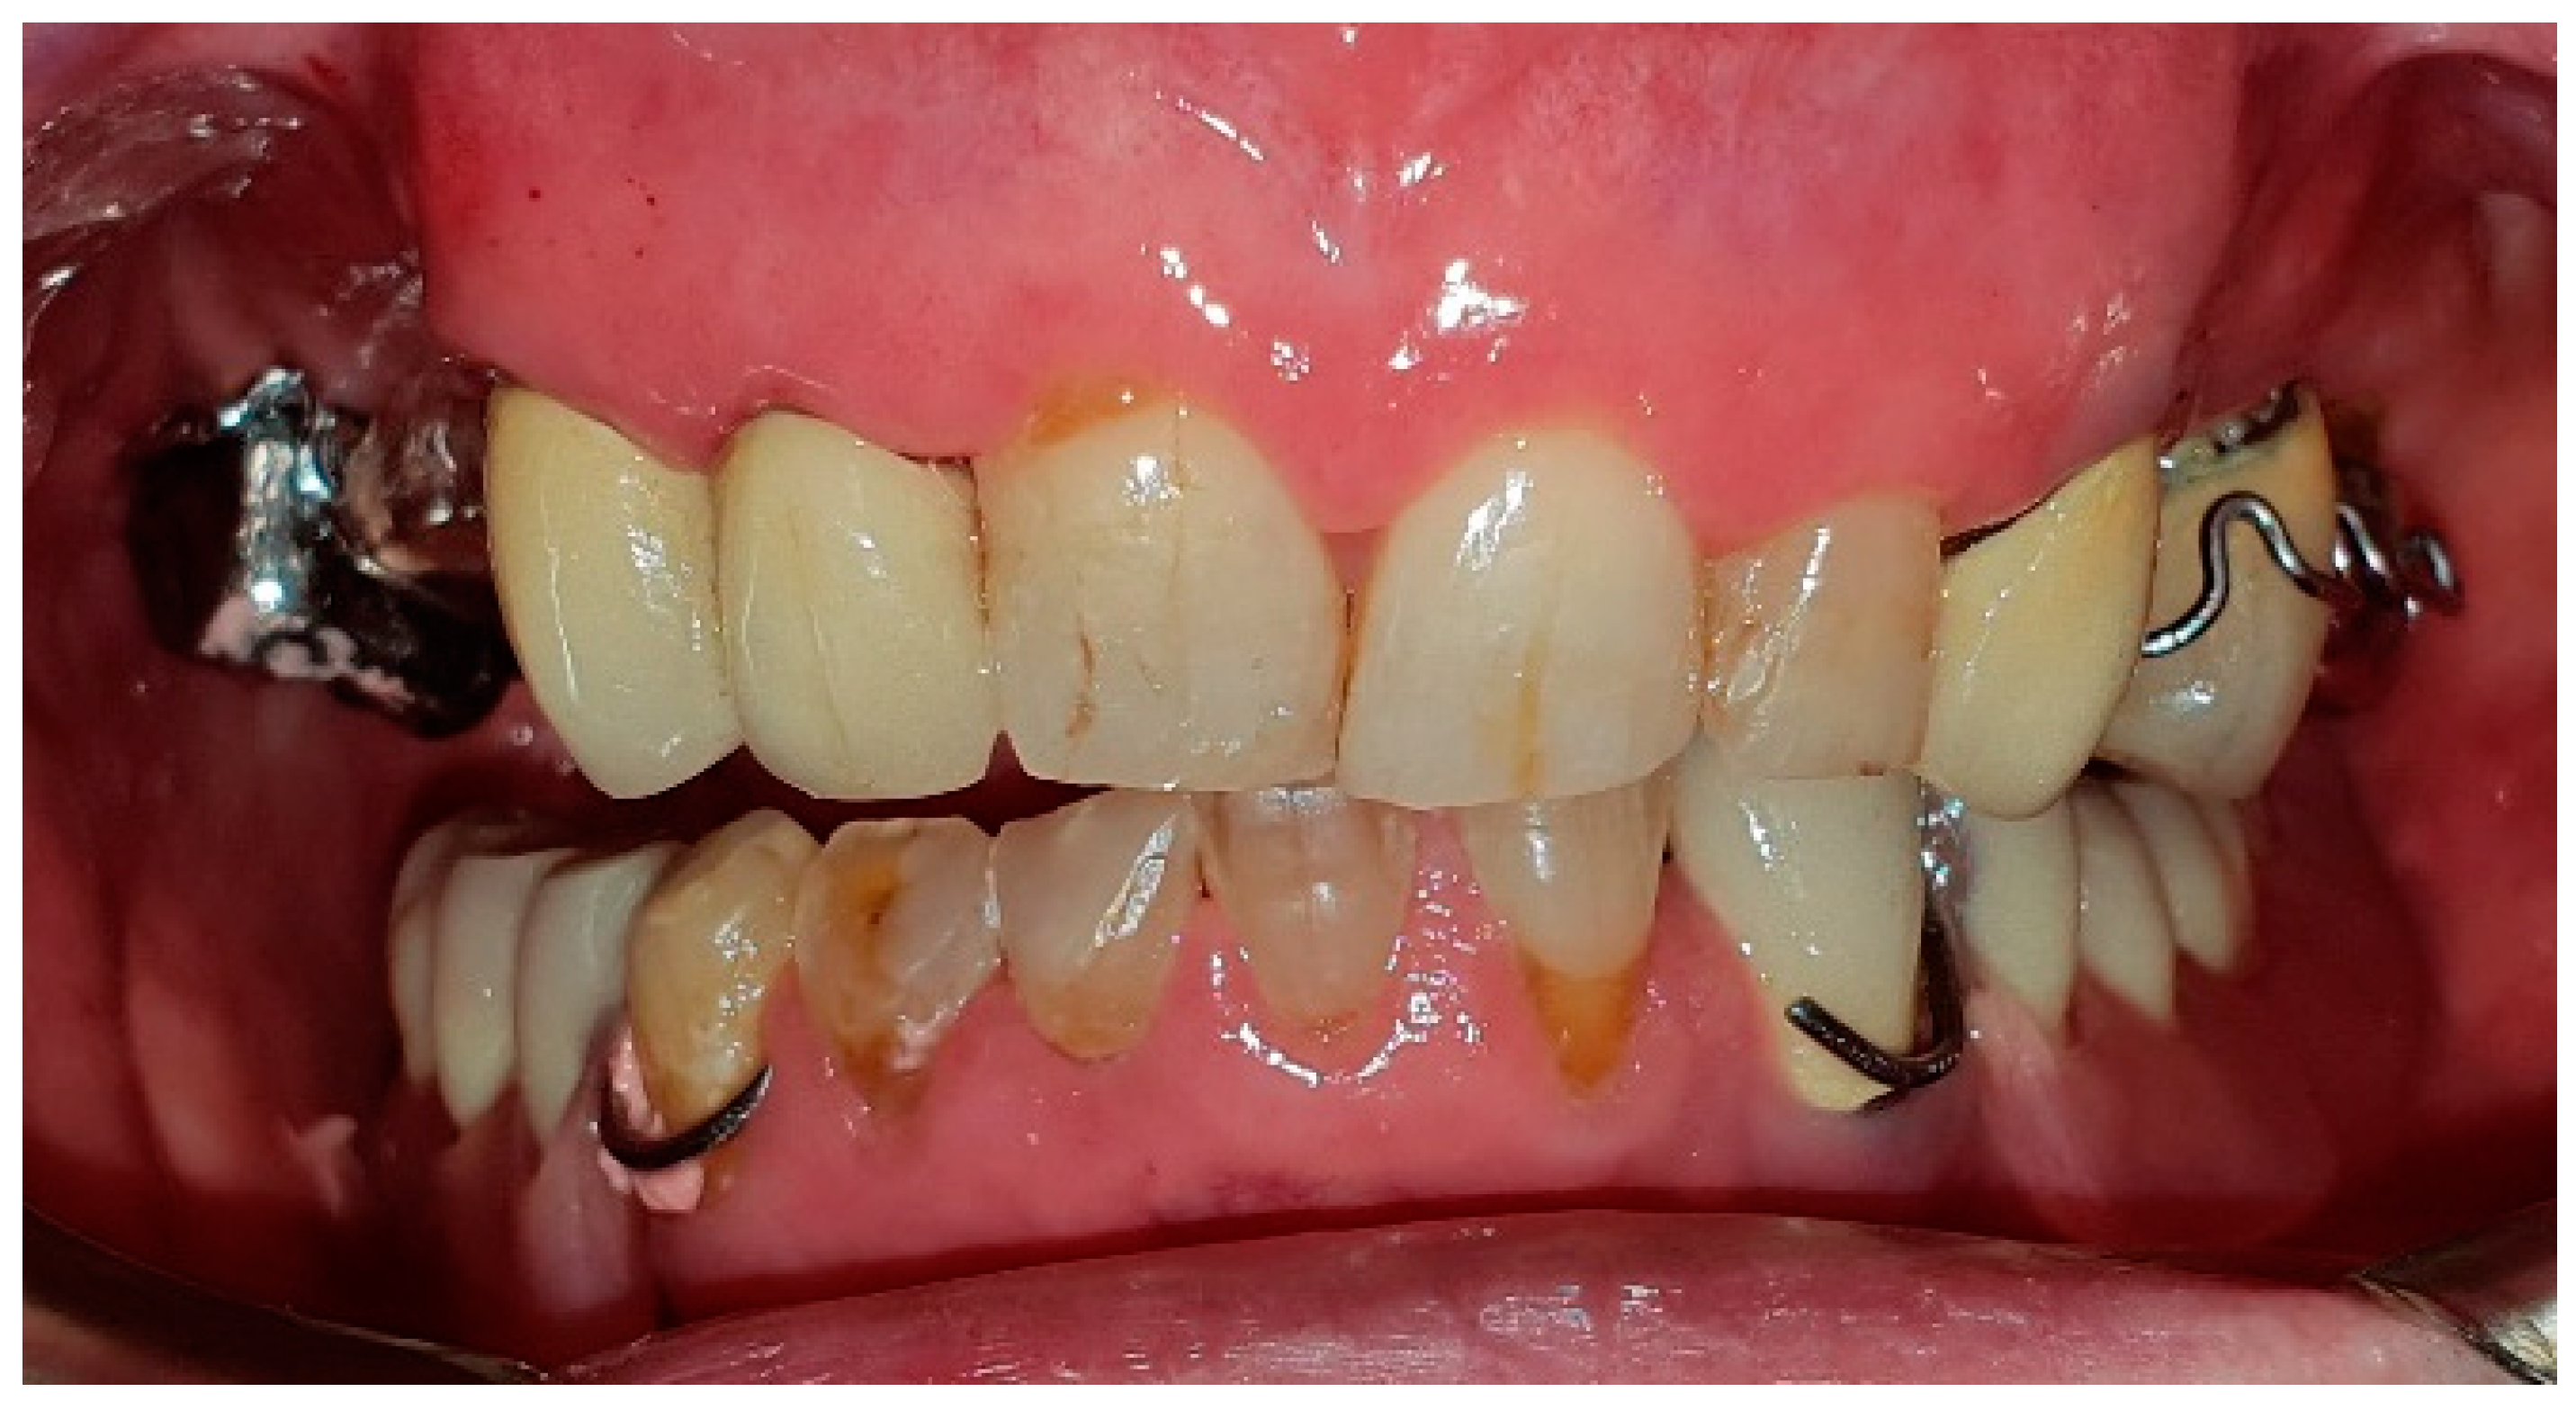

The patient in case n°4 underwent hemimandibulectomy resulting in an extensive bone defect (L1-2-3) that included the conoid process, the angle of the mandible and a portion of the body of the mandible (Figure 13 and Figure 14). Due to the defect, both functional movements of open and closure appear massively deviated: despite the presence of six dental elements (31, 32, and 33 treated endodontically and with a prosthetic crown and 41, 42, and 43), the lack of the coronoid process due to surgical resection does not allow for a more centered position of the mandible, as the surviving segment tends to deviate and pull massively towards the surgical side.

The trajectory of the opening movement presents a further deviation. The deep bite probably represents a worsening factor for the deviation, due to the lack of proprioception (Figure 15).